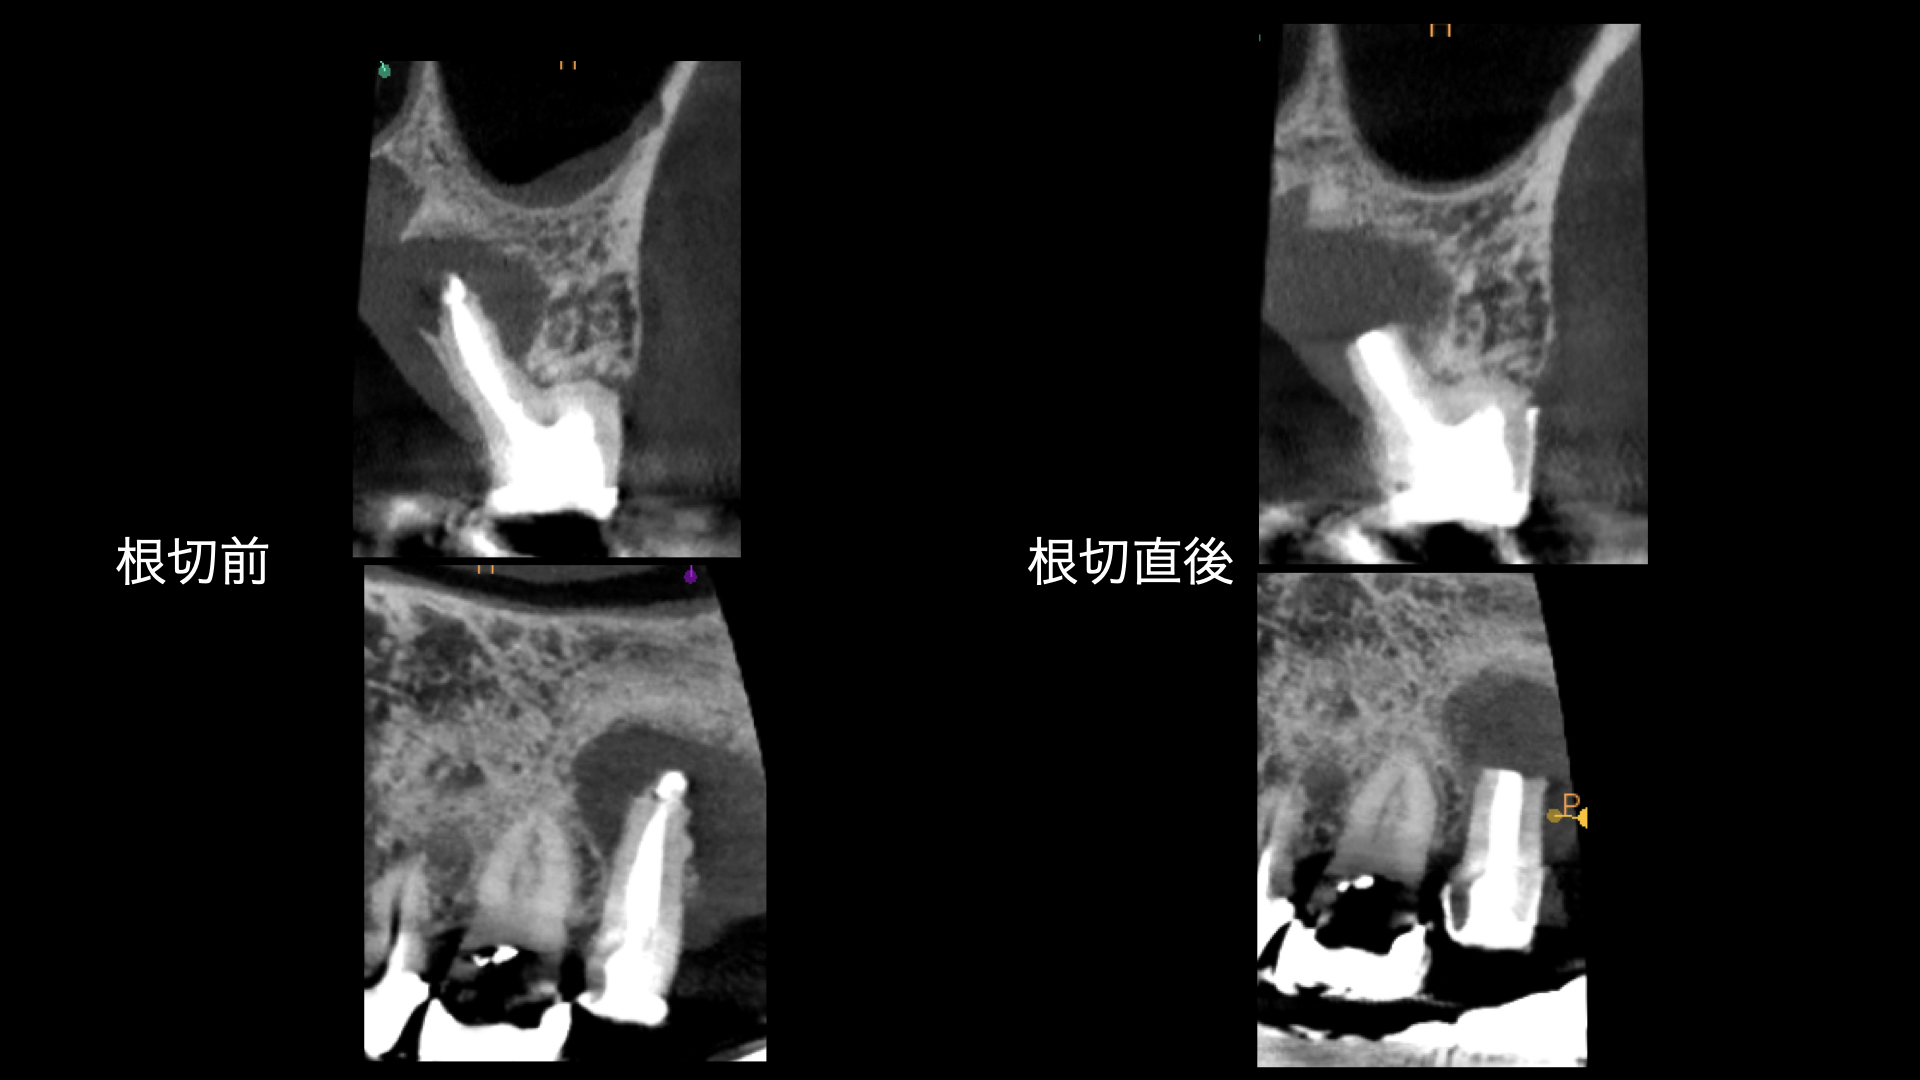

右の画像のCT上で根尖部にかなり大きな透過像があります。

根管治療はマイクロスコープを使用し、根管内は綺麗になった。と判断したので2回でMTAセメントにより根管充填をおこないました。

噛み合わせの反対側(下顎)はインプラント治療をおこなっており、経過をみていましたが全く変化がありませんでした。

術後、歯根は骨に囲まれるように治癒にしました。